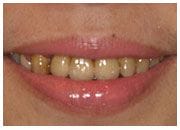

陳女士是上市公司的董事長夫人,時常需要交際應酬,但是前牙的假牙讓她困擾許久,希望尋求自然又美觀的假牙,最後於本診所接受人工植牙的治療,並且使用全瓷牙冠,效果自然,與其他牙齒極為搭配,讓人分辨不出真牙或假牙,陳女士有喝茶的習慣,特別要求假牙顏色不能死白,必須與所有牙齒一致,最後的結果令陳女士相當滿意。

治療後